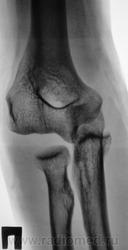

Травма.  Пациент направлен на рентгенографию локтевого сустава.

Аглицким владею (как писал раньше, заполняя различные совеЦкие анкеты) со словарем (хотя уровень этого знания таков, что никакогословаря не хватит), поэтому не могу прочитать предыдущий комментарий. А по поводу случая - я так понимаю медиальный вывих предплечья.

кости предплечья, сохраняя свое положение по отношению друг к другу, смещены в медиально и каудально. Дистальный эпифиз плечевлй кости с латеральной стороны лежит свободно (так можно писать??) Смещение в медиальную сторону составляет примерно половину ширины головки лучевой кости. Суставные поверности плечевой и локтевой кости не соприкасаются. Перелом не определяется.

Заключение: медиальный вывих предплечья ?